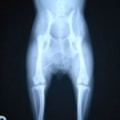

膝蓋骨脱臼は膝関節における膝蓋骨の内外側の脱臼と定義されるが、時として単純な内外の脱臼ではなく、膝蓋骨が大きく前方に浮き上がるように脱臼する場合がある。特にトイプードルやポメラニアンといった犬種に多く認められる。

内側脱臼に加えて前方への浮き上がりを矯正する為に、従来より脛骨粗面転移により膝蓋靭帯を外方と下方に引っ張り、固定する方法を選択する。膝蓋骨の前方への浮き上がりが軽度の場合は、従来法ではなく関節包の縫縮で対応していた。しかし、一部の症例で膝蓋骨の動きが悪くなり伸展機構が円滑に機能せずロボット様歩行になるケースがあった。

その為、膝蓋靭帯自体を縫縮する方法を採用した。この方法により、膝関節の伸展機構を妨げず膝蓋骨の軽度の浮きを矯正することが可能となった。

本症例の経過は良好である